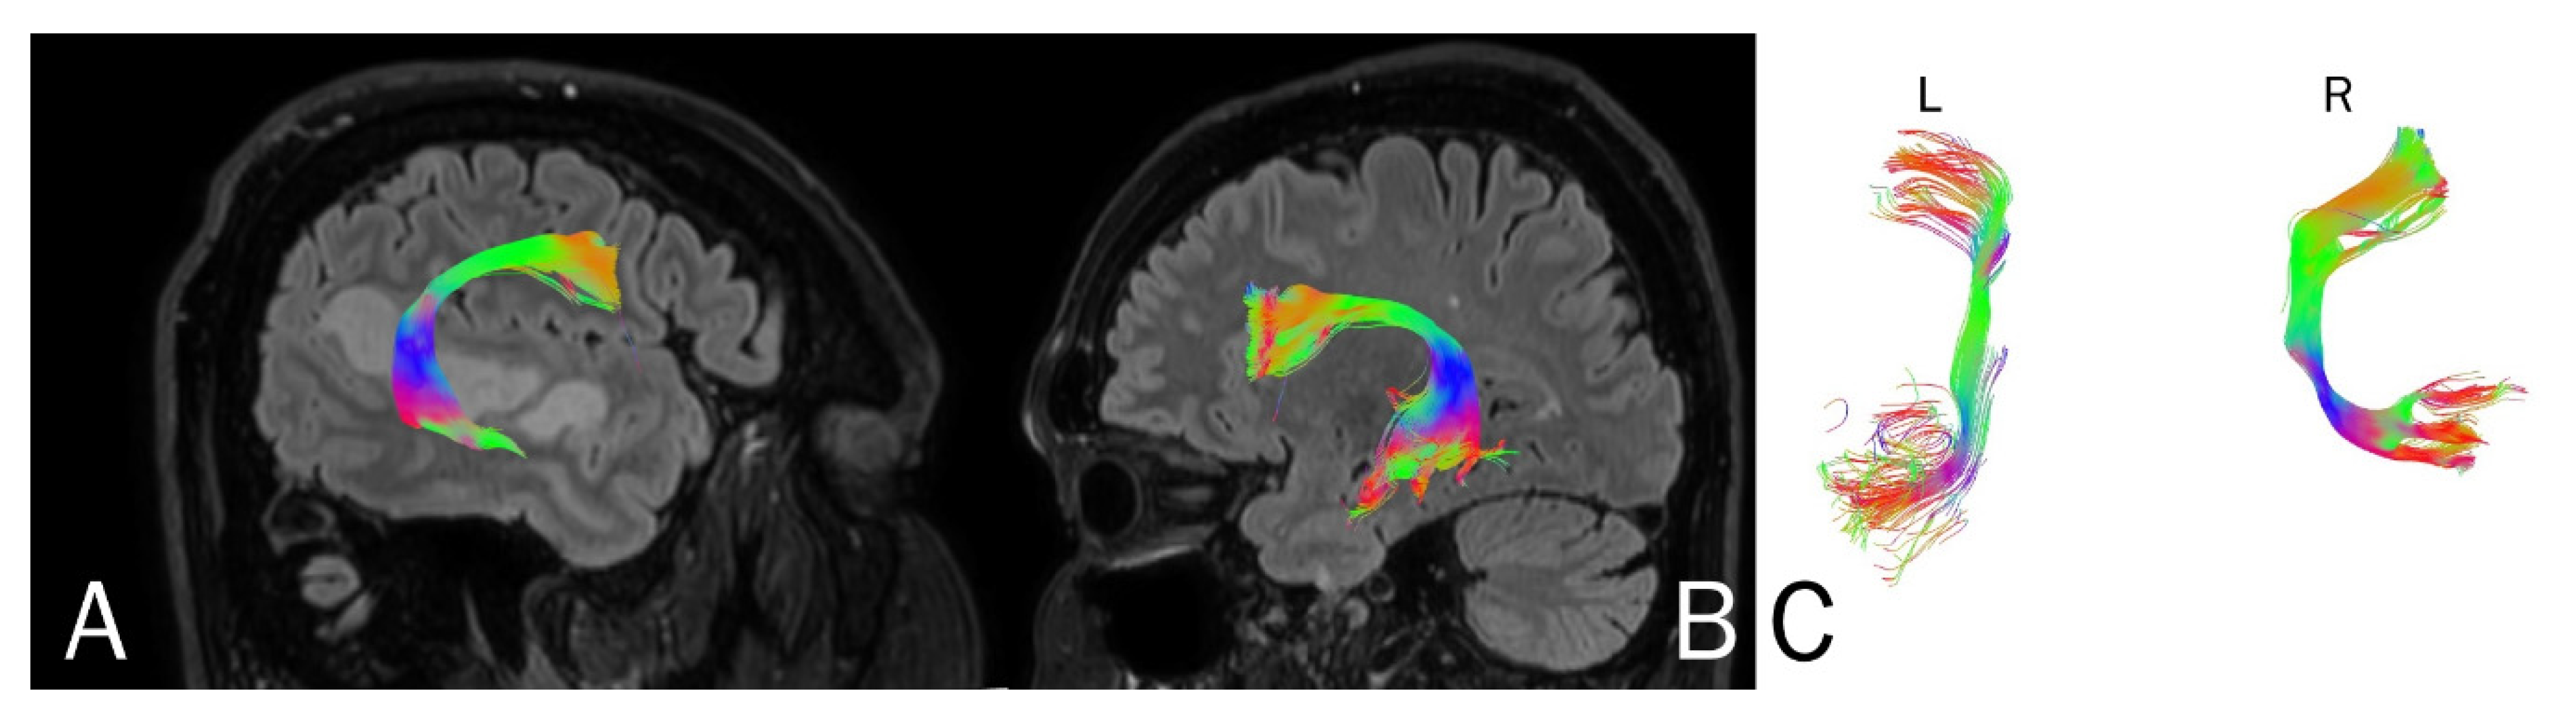

| Parameters | Left side | Right side | Left side | Right side |

| Number of fibers | 148 | 183 | 155 | 152 |

| Volume of tract [mm2] | 13305 | 16440 | 14400 | 16338 |

| Length of tract [mm] | 88.5 | 98.3 | 87.5 | 97.1 |

| FA | 0.675 | 0.895 | 0.705 | 0.880 |